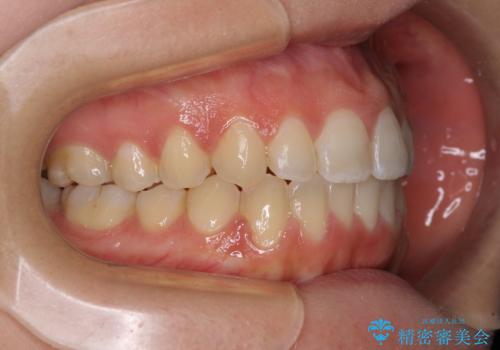

【モニター】オープンバイトをインビザラインで矯正治療

- 前歯の上下スペースによる食べにくさを気にして来院された患者様です。

インビザラインにより上下の前歯の隙間を閉じていくこととしました。

前歯のデコボコの解消と並行して上下の奥歯を圧下させるようにすることで、前歯を接触させるように計画しました。

上下の隙間に舌が入り込むことがオープンバイトの原因であったため、舌の筋肉のトレーニングも並行して行い、後戻りの抑制を図りました。